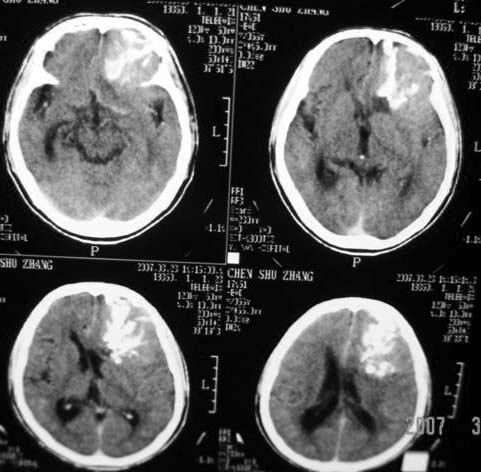

标题: CT7268:左额顶部病变增强片. [打印本页]

标题: CT7268:左额顶部病变增强片.

比较典型的少枝胶质细胞瘤ct表现,局部额骨垂直板有侵蚀变薄。

左额叶病灶内条片状高密度是钙化吗?是的话考虑少支胶质瘤可能大。不然有脑血畸形伴出血可能。

左侧额顶叶有条带状钙化的不规则形占位,增强呈不均匀轻度强化,局部颅骨受侵蚀变薄,典型的少支胶质细胞瘤。

比较典型的少枝胶质细胞瘤ct表现,局部额骨垂直板有侵蚀变薄